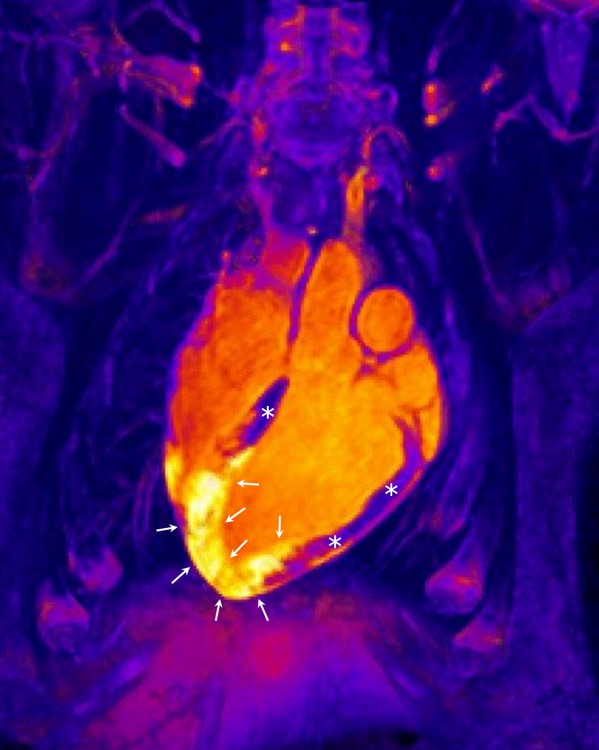

El tejido adiposo epicárdico podría ser clave como protector frente a la insuficiencia cardíaca